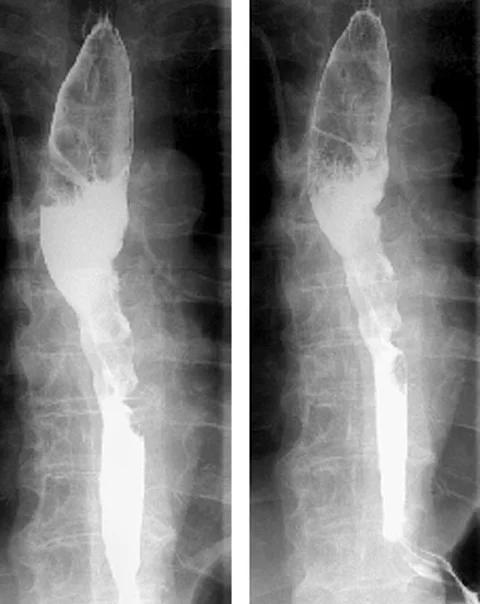

Der Patient stellt sich mit Schluckstörungen vor. Nachdem Sie die Aufnahmen des Ösophagusbreischlucks sehen, haben Sie einen bestimmten Verdacht. Welchen?

Der Ösophagusbreischluck zeigt eine Raumforderung im Ösophagus. Doch nur eine der drei Antwortmöglichkeiten ist die korrekte Diagnose. Lagen Sie richtig?